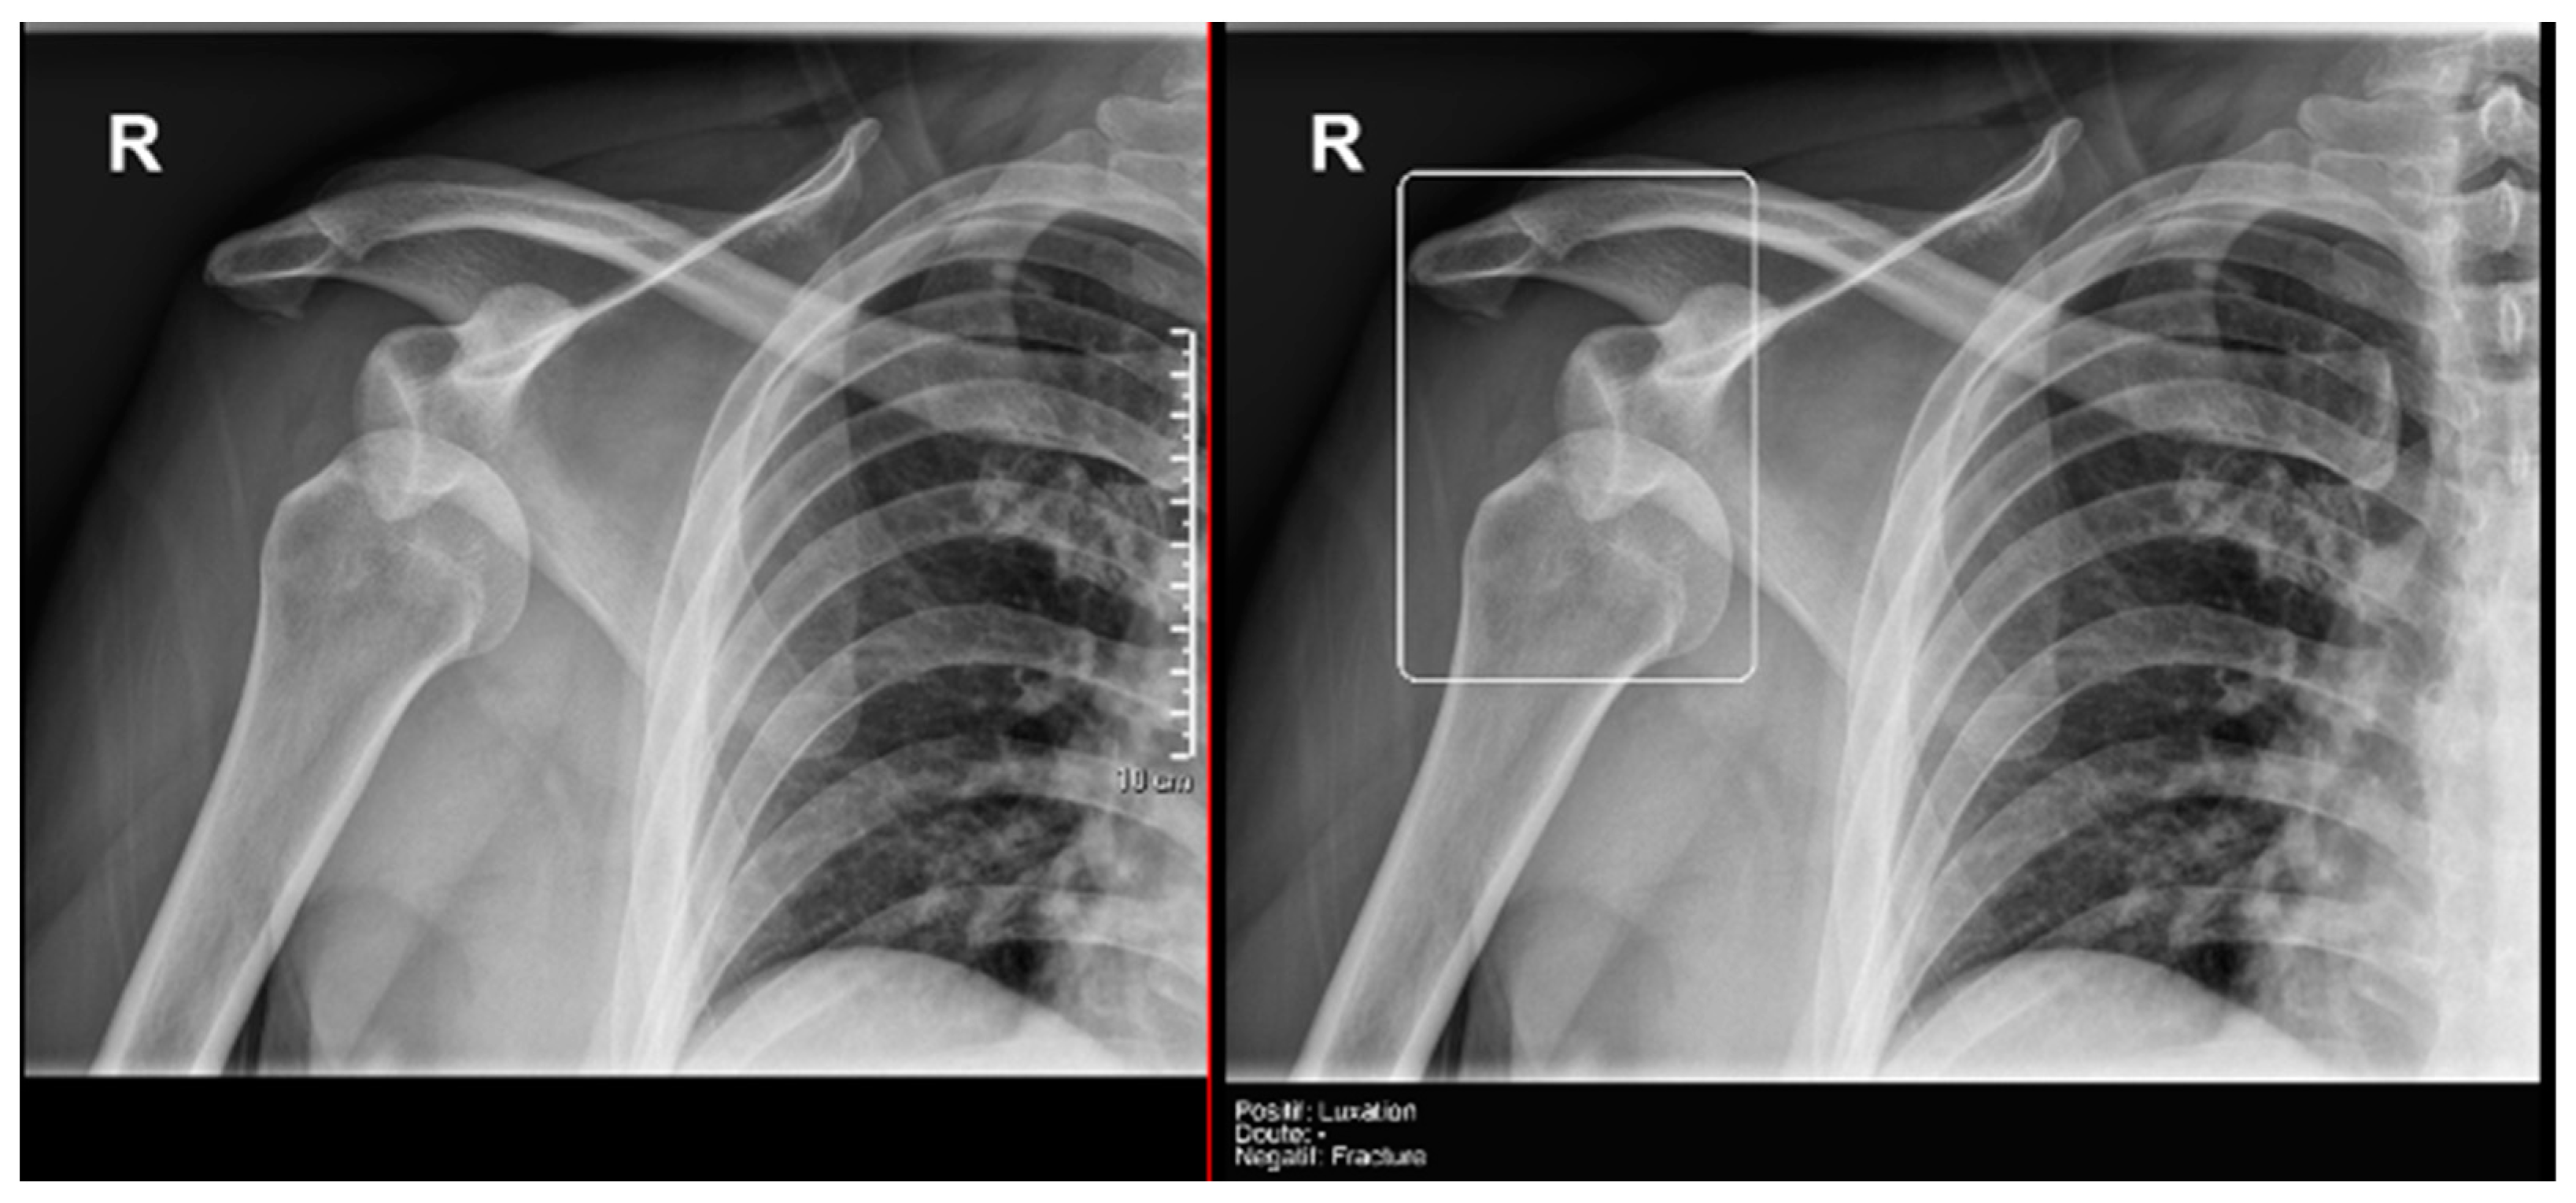

3.3.2. Acute Joint Dislocation